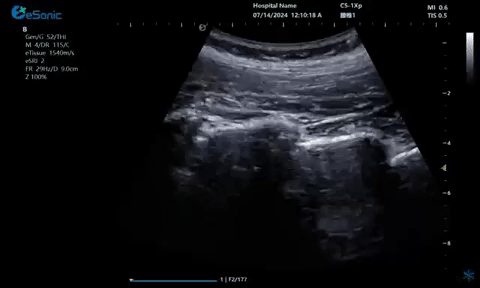

超声引导下肋间神经阻滞切面

9.1.gif